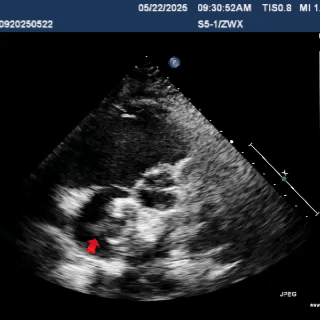

术中复测缺损大小

缺损大小为24.1mm

超声多切面观察封堵器位置形态,封堵器骑跨于缺损左右两侧

主动脉短轴切面显示封堵器呈Y字型抱住主动脉根部,夹持稳定

剑下两房心切面下观察,封堵器位置正确、形态良好

该病例术中复测房间隔缺损大小为24mm,断缘距下腔静脉14.2mm,距上腔静脉15.8mm,前后边缘各为10.1mm、16mm。房水平左向右分流。

封堵器左右盘面释放后,主动脉短轴切面显示封堵器呈Y字型抱住主动脉根部,通过牵拉实验,封堵器位置固定,未见明显位移及形变,多切面观察封堵器形态良好,无残余分流,封堵手术成功。